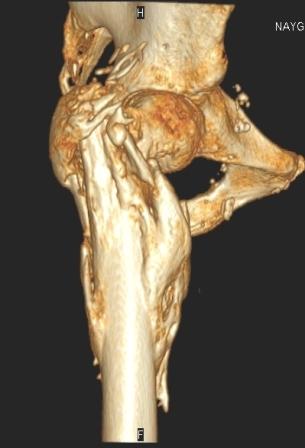

[Ortho] Сросшийся со смещением чрез-подвертельный перелом

----------- следущая часть -----------

Вложение не в текстовом формате было извлечено…

Имя     : уменьш (9).jpg

Тип     : image/jpeg

Размер  : 19096 байтов

Url     : http://weborto.net:8080/pipermail/ortho/attachments/20091031/f055a08c/attachment-0009.jpg